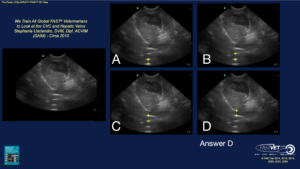

Quiz – Can You Properly Identify the CVC?

Note the image to the left without any arrows is the patient’s DH view. In A) – D) and arrow is placed with possible locations of the CVC. Which of these views correctly identifies the CVC?